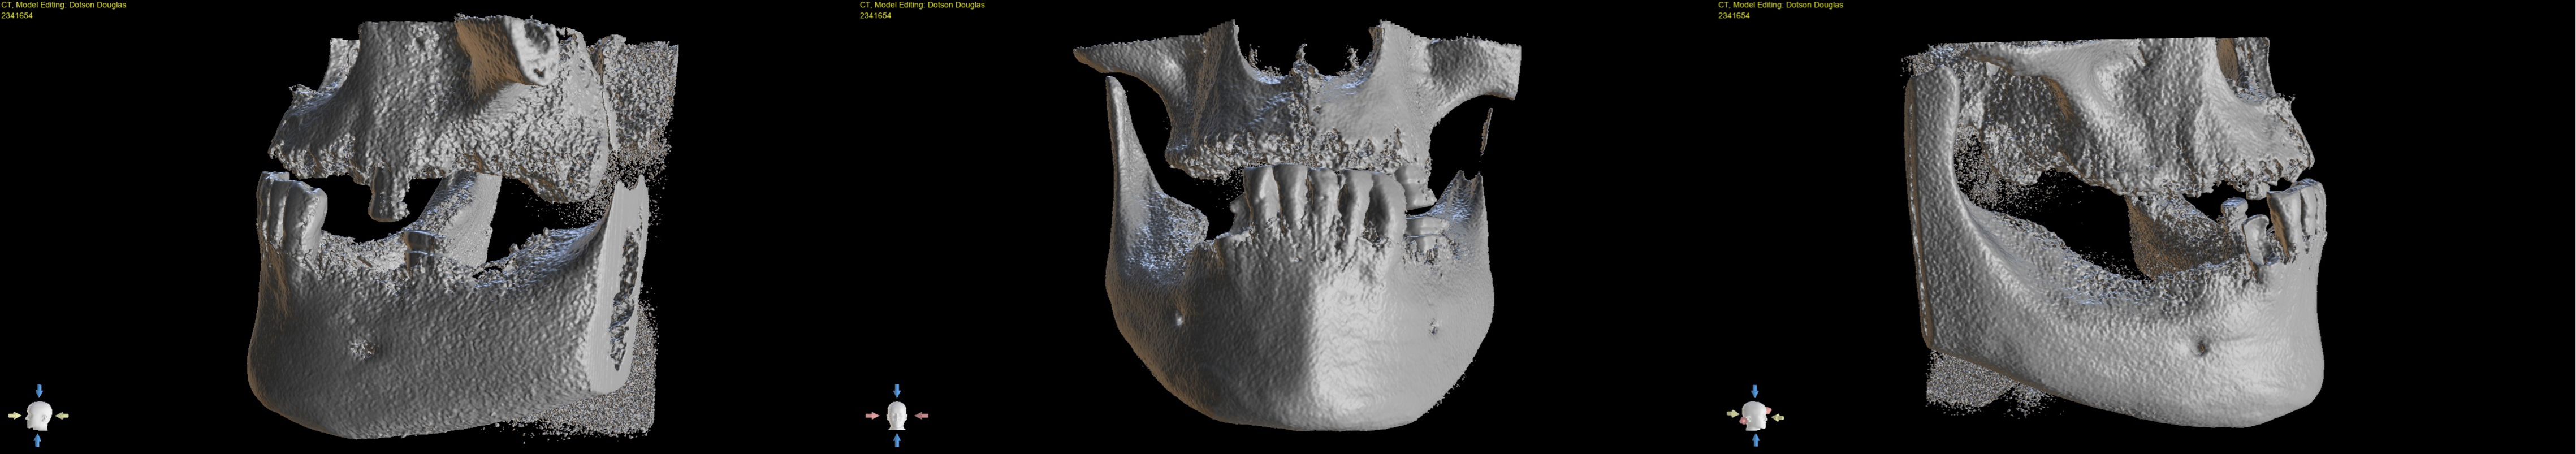

Figure 3 shows 3D Images of the CBCT scan

After examining the patient's current condition, Dr. Glen confirmed the treatment plan of removing the remaining implants and existing teeth. Followed by placing 6 upper implants and 6 lower implants with 2nd-day delivery to minimize the wait time as much as possible before the final restorative plan of placing full-arch upper and lower dental implants. Dr. Glen was able to use the data collected by an intraoral scanner to create the design for full-arch upper and lower dental implants.